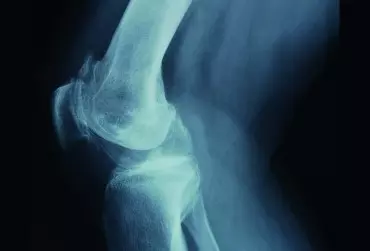

Rehabilitacja po usunięciu stabilizacji gwoździem śródszpikowym

Złamaniem nazywa się całkowite przerwanie ciągłości tkanki kostnej. Towarzyszą one człowiekowi od zawsze. Średnio występowanie złamań w populacji określa się na 13–36 przypadków na 1000 osób w skali roku i najczęściej dotyczą one mężczyzn. Złamania mogą powstać na skutek urazów pośrednich, bezpośrednich, niskoenergetycznych, bez urazu (np. złamania patologiczne lub na skutek osteoporozy) lub na skutek sumujących się mikrourazów, tzw. złamania zmęczeniowe [6, 10].